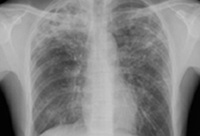

Pulmonary tuberculosis

Right-sided pleural effusion

From the personal collection of David Horne and Masahiro Narita; used with permission